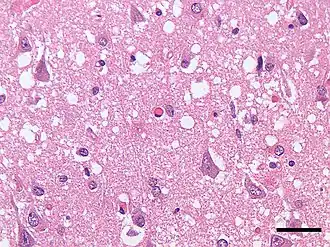

• морфологическое и гистологическое исследование тканей головного мозга (коры, подкорковых ядер) при аутопсии (посмертная диагностика).